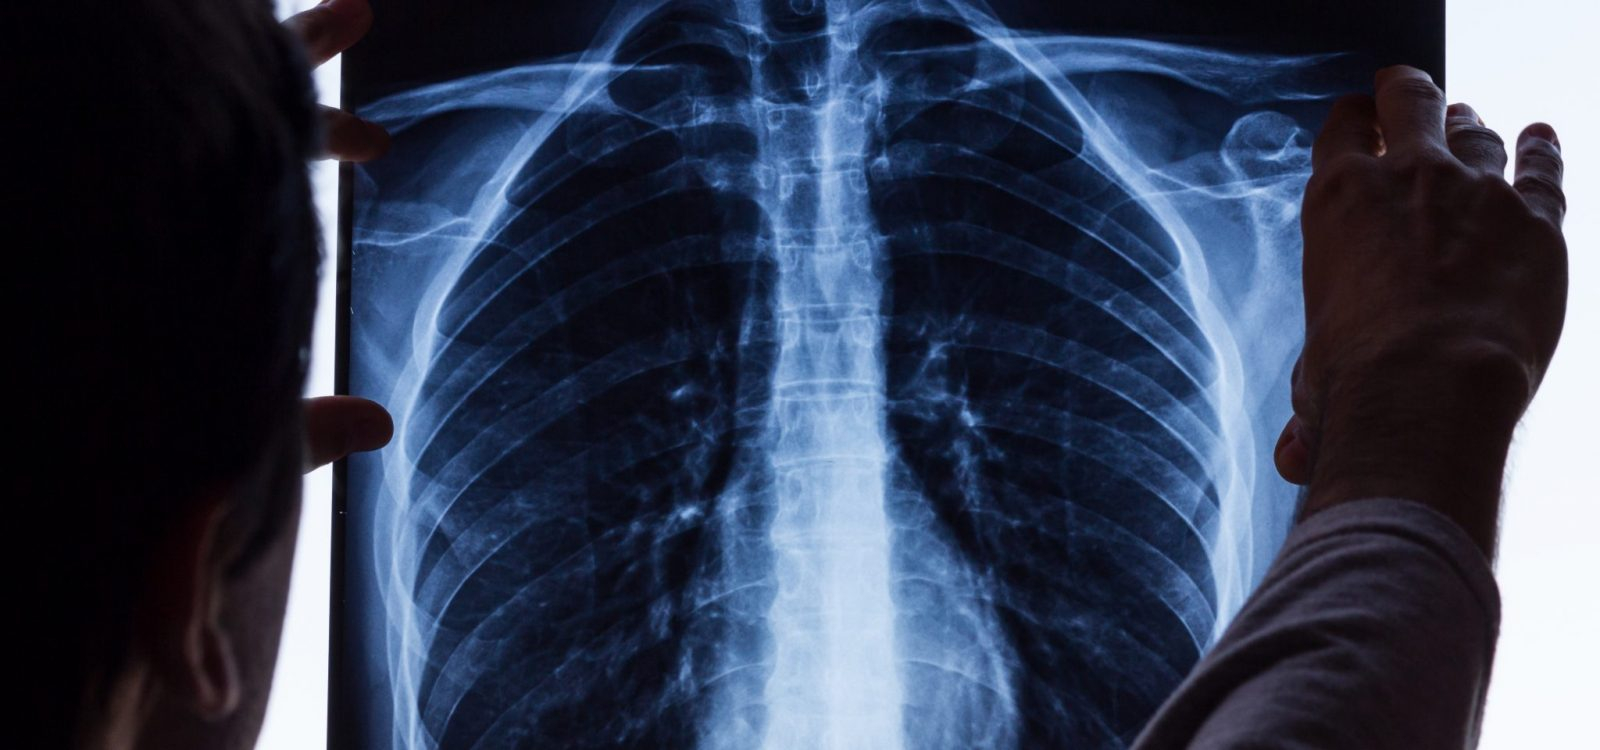

Un gălăţean care a lucrat în siderurgie ca turnător-formator a fost diagnosticat cu silicoză în stadiul al III-lea, în 2019, afecţiunea fiind declarată boală profesională, conform Inspectoratului Teritorial de Muncă (ITM) Galaţi. Acesta este singurul caz de boală profesională înregistrat, anul trecut, în judeţul nostru. Silicoza este o boală determinată de factori de mediu. Mai exact, afecţiunea apare în urma inhalării, pentru o perioadă îndelungată de timp, a pulberilor cu conţinut crescut de bioxid de siliciu liber cristalin.